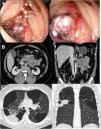

We report the case of a 40-year-old man, COPD GOLD II, with bullous emphysema who was admitted for upper gastrointestinal bleeding (UGIB) and a hemoglobin of 5g/dl. Gastroscopy (Fig. 1A) revealed an actively bleeding ulcer (Forrest IB) in the 3rd segment of the duodenum. An abdominal CT scan was performed (Fig. 1B), showing wall thickening in the regions and adjacent enlarged lymph nodes. Histological and immunohistochemical studies were consistent with high-grade primary pulmonary adenocarcinoma metastases.

(A) Endoscopic image of a large duodenal ulcer with active oozing hemorrhage (Forrest IB). (B) Computed axial tomography image of the abdomen with lesion in the 4th segment of the duodenum with adjacent lymph node blockage. (C) Computed axial tomography image of the chest showing a tumor in the posterior segment of the right upper lung lobe. Extensive bulbous emphysema in upper lobes.

Chest CT scan (Fig. 1C) located the primary pulmonary tumor in the right upper lobe with right hilar and left axillary lymphadenopathies. The histological study of the axillary lymph node was consistent with primary pulmonary adenocarcinoma metastasis strongly positive for PD-L1. The patient was treated with endoscopy and radiotherapy without success, so to achieve hemostasis, a duodenal prosthesis was placed by endoscopy, resulting in progressive recovery and control of gastrointestinal bleeding. Treatment with pembrolizumab then began.